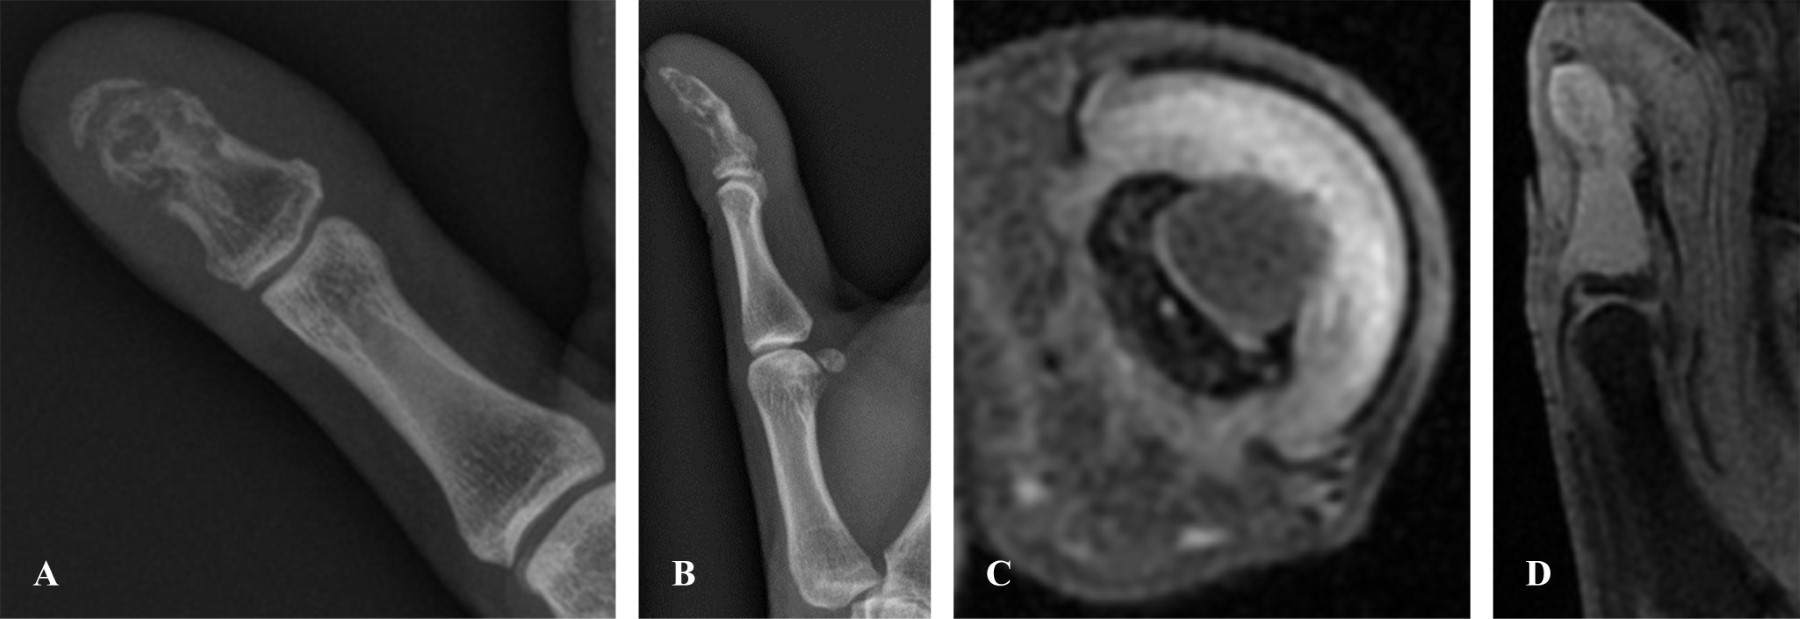

Se amplió el estudio de imagen con una resonancia magnética que informaba de una lesión lítica con rotura de la cortical dorsal sin alteración del remanente óseo de la base de la falange distal, por lo que se clasificó como una lesión focal abscesificada (Figura 4) que también correspondería con un signo de la penumbra. Ante tales hallazgos, esta vez con la sospecha de quiste epidermoide óseo sobreinfectado, se programó la intervención quirúrgica.

Figura 4